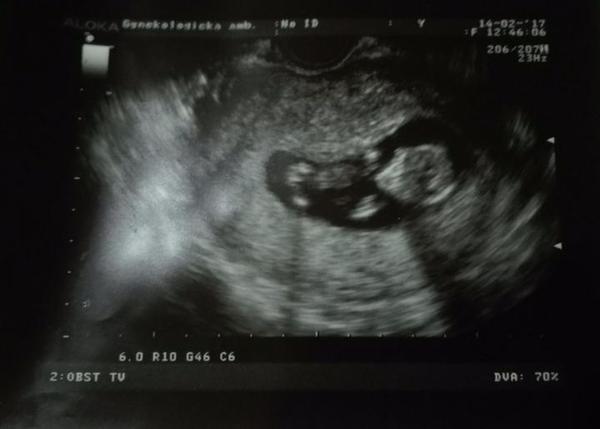

@dadulka271 tak, našla som celkom rýchlo. pekná postupka. 😉 prvý je 1. deň meškania ms, druhý je na ďalší deň, tretí je 8 dní meškania a posledný testík je 12 dní meškania. a náš drobček v 13tt. 🙂